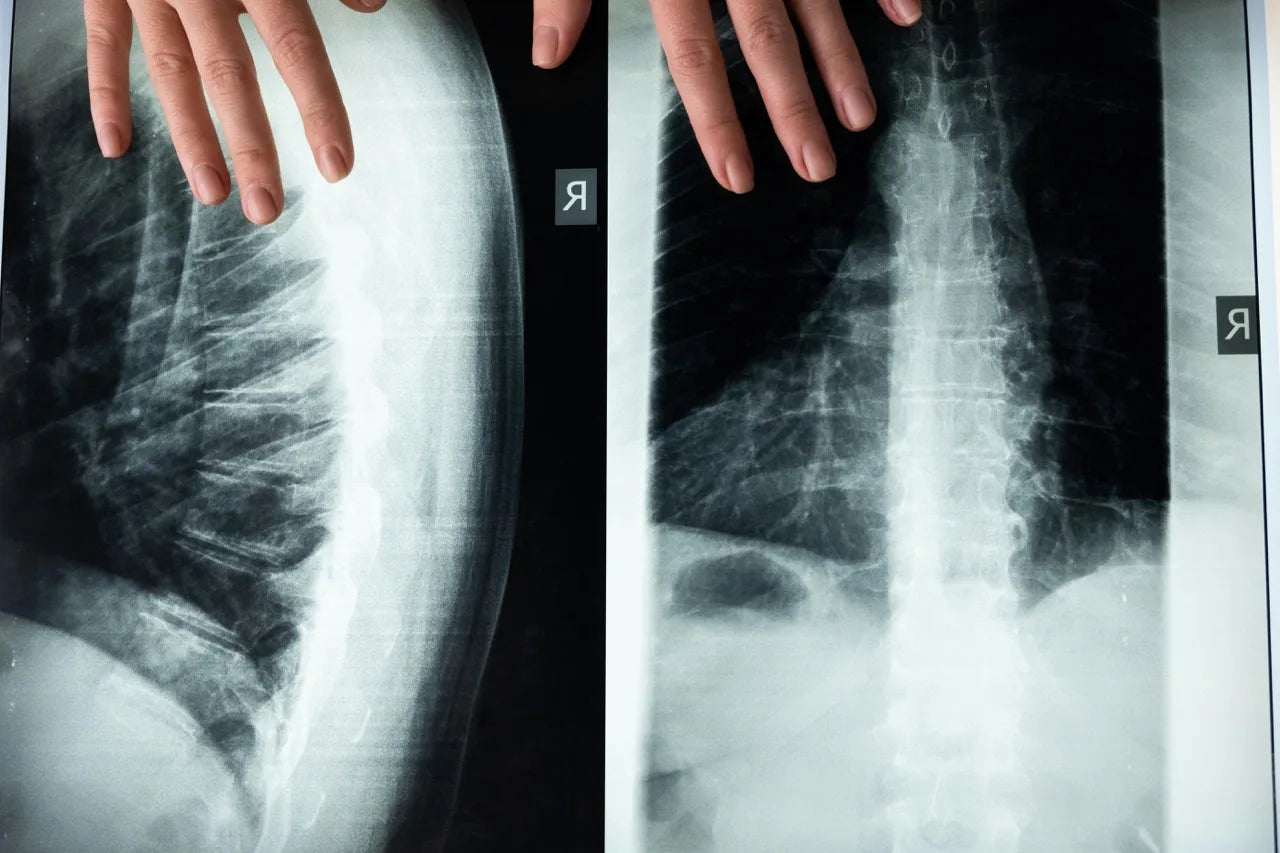

Osteoporose, eine Krankheit, die durch schwache und brüchige Knochen gekennzeichnet ist, wird oft als eine Frauenkrankheit angesehen (General, 2004). Doch auch Männer, insbesondere jene mit Hypogonadismus, sind gefährdet. Studien haben gezeigt, dass Männer mit niedrigen Testosteronspiegeln ein erhöhtes Risiko für Frakturen haben, insbesondere an Hüfte, Wirbelsäule und Handgelenk. Diese Frakturen können schwere gesundheitliche Folgen haben und die Lebensqualität erheblich beeinträchtigen (Golds et al., 2017).

Die Wirbelsäule ist ebenfalls gefährdet, da Frakturen in diesem Bereich zu chronischen Schmerzen, eingeschränkter Beweglichkeit und einer Verschlechterung der Körperhaltung führen können. Handgelenksfrakturen, die oft als weniger schwerwiegend angesehen werden, können dennoch erhebliche Beeinträchtigungen im täglichen Leben verursachen, insbesondere wenn sie wiederholt auftreten oder nicht richtig heilen. Die Prävention und frühzeitige Behandlung von Knochenschwäche bei Männern mit Hypogonadismus ist daher von entscheidender Bedeutung, um ihre Lebensqualität zu erhalten und schwerwiegende gesundheitliche Folgen zu vermeiden.

Ein weiteres wesentliches Instrument zur Beurteilung der Knochengesundheit ist die Knochendichtemessung, auch bekannt als DXA-Scan (Dual-Energy X-ray Absorptiometry). Dieser nicht-invasive Test misst die Knochendichte und hilft, frühe Anzeichen von Osteoporose oder einer verminderten Knochendichte zu erkennen, bevor es zu Frakturen kommt. Der DXA-Scan liefert präzise Informationen über die Knochendichte in verschiedenen Teilen des Skeletts, insbesondere in der Hüfte, der Wirbelsäule und dem Handgelenk, die am anfälligsten für Frakturen sind (Blake & Fogelman, 2007).